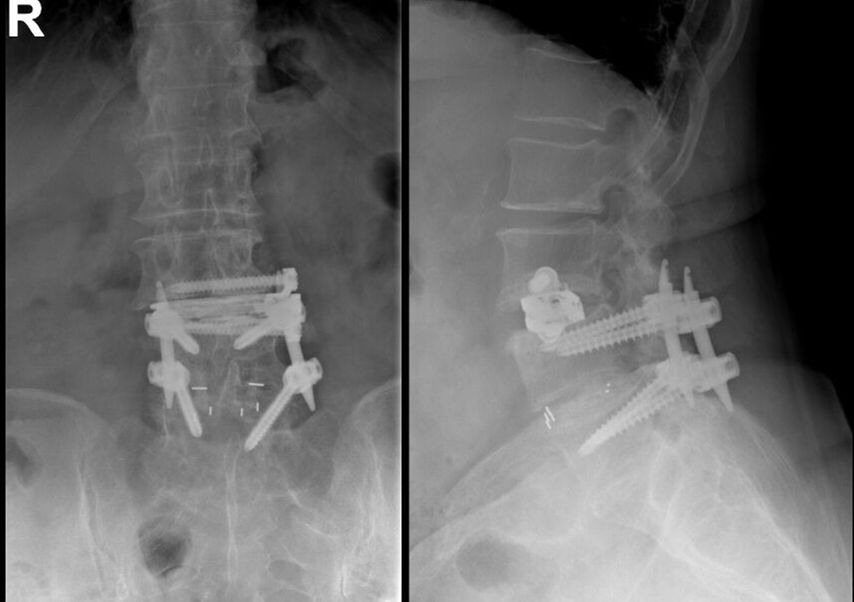

Fallbeispiel 1

Beispiel für die Implantation zervikaler Pedikelschrauben. In diesem Fall kam es bei einem 61-jährigen Patienten 10 Jahre nach anteriorer zervikaler Diskektomie und Fusion (ACDF) C4/5 und ventraler Verplattung C4–6 zu einer Ankylosierung auch von C6/7. Nach Sturz kam es zu einer Fraktur bei C6/7 mit begleitender Bogenfraktur und auch Beteiligung der dorsalen Ligamenta (Abb. 1 und 2). Klinisch bestanden ausgeprägte Nackenschmerzen und kein neurologisches Defizit. Es wurde die Indikation der dorsalen Verschraubung von C4 auf Th1 gestellt. Intraoperativ wurde routinemäßig zusätzlich eine kleine Referenzschraube in einer Lamina – entfernt von der Dornfortsatz-Referenzklemme für die Navigation – gesetzt. Mit dieser konnte intraoperativ die Genauigkeit der Navigation exakt überprüft werden (Abb. 4 und 5). Mittels navigierter High-Speed-Fräse wurden die Schraubenkanäle vorgebohrt (Abb. 6), im Anschluss wurde der Bohrkanal ausgetastet und die Schrauben wurden implantiert. Abbildung 7 zeigt eine Röntgenkontrolle 3 Monate postoperativ.

Abb. 4: Screenshot der Navigationssoftware intraoperativ (Stealth Station S7). Es erfolgt die intraoperative Verifizierung der Navigationsgenauigkeit mittels kleiner Schraube in der Lamina, positioniert idealerweise entfernt von der Dornfortsatz-Referenzklemme. Die navigierte Fräse wird im Situs exakt auf die Schraubenmitte gerichtet, und die Navigation bestätigt die Genauigkeit | |